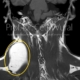

Otuz sekiz yaşında erkek hasta sağ kulak altında üç ay kadar önce fark ettiği şişlik nedeniyle bize başvurdu. Yapılan muayene ve MR inceleme sonucunda sağ parotis tükürük bezinin yüzeysel lobundan derin lobuna doğru uzanan 25x15mm boyutta tümör saptandı. Bu tarz tümörlerin cerrahisi yüzeysel lobda yerleşmiş tümörlere kıyasla biraz daha zor ve yüz sinirinin korunması açısından riskli olmaktadır. Hastamıza genel anestezi altında sinir monitör cihazı kullanılarak sağ parotidektomi ameliyatı yapıldı ve yüz siniri korunarak tümör kapsülü sağlam halde çıkartıldı.